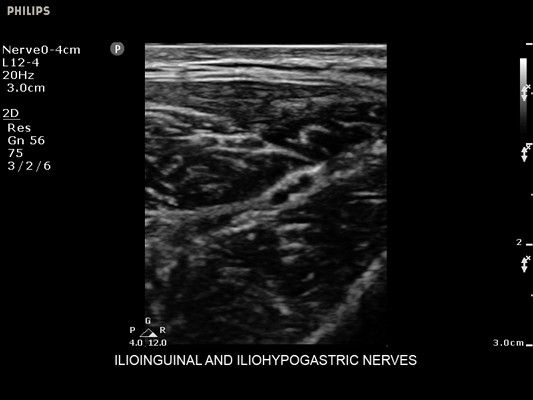

• Диагностика нервов

• Улучшение визуализации иглы для линейных датчиков - Да

• Линейный УЗИ датчик Philips L12-4